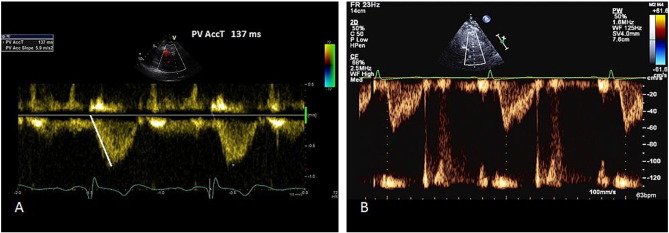

Pulse wave of RVOT normally produces a dome shape, but in patients with pulmonary hypertension, there is rapid rise to peak, resulting in shorter acceleration time [17] . A mid-systolic notching could also indicate pulmonary hypertension [17] .

A pulse wave signal of pulmonic forward flow is obtained at end expiration, just proximal to the pulmonary valve in the parasternal short axis view. The Doppler sample is placed in such a way that the obtained signal has a closing snap but not an opening snap. The quality of the signal is very important and maximum sweep speed must be used to increase accuracy. Furthermore, there should not be spectral broadening.

Right ventricular outflow tract (RVOT) acceleration time is measured from the beginning of the flow to the peak flow velocity (Fig. 4 ). It is important that the marker is placed at the peak first and then tracked back to the onset of flow, as the aim is to measure time taken to peak velocity and not the propagation. A value of > 130 ms is normal, while < 100 ms is highly suggestive of pulmonary hypertension [18] . Mean pulmonary pressure is calculated by the formula: mPAP = 90 − (0.62*ATRVOT ). For example, if the ATRVOT is 80 ms, the mPAP = 90 −(0.62*80), that is 40.4 mmHg (normal < 25 mmHg). On the other hand, if the ATRVOT is 137 ms (as in Fig. 4 ), then the calculated mPAP is 90 −(0.62*137) = 5.06 mmHg.

|

Fig. 4. RVOT acceleration time method for assessing pulmonary pressure. A—Pulmonary acceleration time measurement. B—Rapid rise and mid-systolic notching suggesting elevated pulmonary pressure. |

Heart rates outside of the normal range (< 60 or > 100 bpm) may reduce the accuracy of this technique. However, when the mean PAP exceeds 25 mmHg, RVOT acceleration time is accurate even in tachycardia [19] and [20] . More often, the slope of the pulse wave Doppler trace is measured, rather than the time taken from onset to peak velocity. This usually leads to underestimation of the RVOT acceleration time.